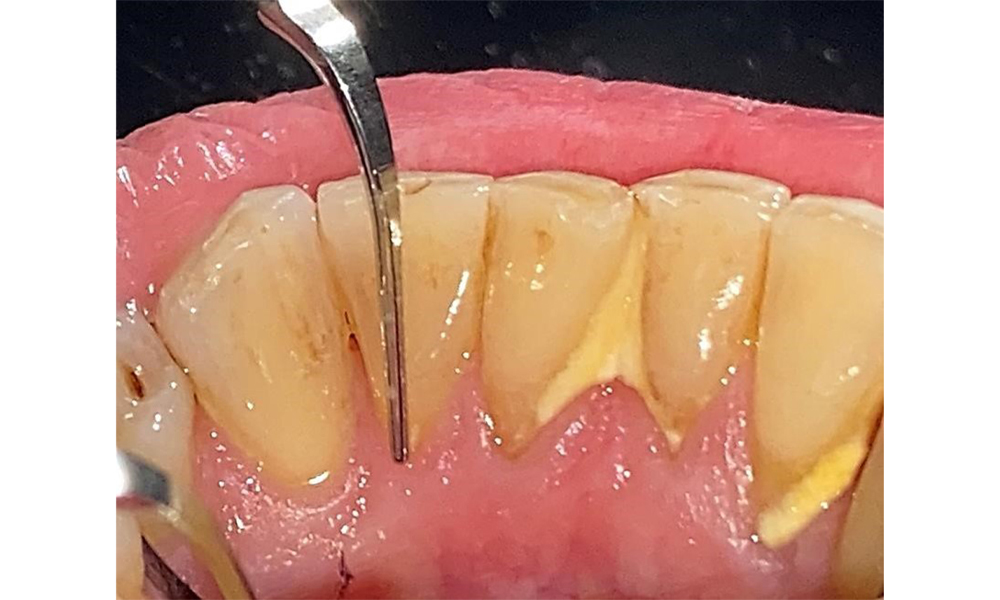

The patient has stage II, grade B periodontitis (5). At 1 to 3 mm, the clinical probing depths were within the physiological range. Localized probing depths of 5 mm were observed on the mesiopalatal aspects on both 17 and 27. There are generalized recessions of 1–3 mm with partial loss of the interdental papillae (Fig. 2, Fig. 3, Fig. 4)

The documentation of periodontal findings, including pocket depth probing and bleeding status, is mandatory during each dental appointment due to the presence of periodontitis (Fig. 8). This will record the individual therapeutic needs and facilitate a rapid response to any progression of the pre-existing periodontitis.

There are no limitations regarding the choice of instrumentation methods. Regular supragingival and subgingival instrumentation is essential to prevent disease progression due to the pre-existing periodontitis and high risk of recurrence. There are no limitations placed on the selection of instruments for mechanical biofilm removal from a general medical perspective, and removal should be performed as needed. Hard and mineralized plaque, such as calculus and concretions, should be removed using manual instruments or sonic/ultrasonic scalers (Fig. 9) (8, 9).